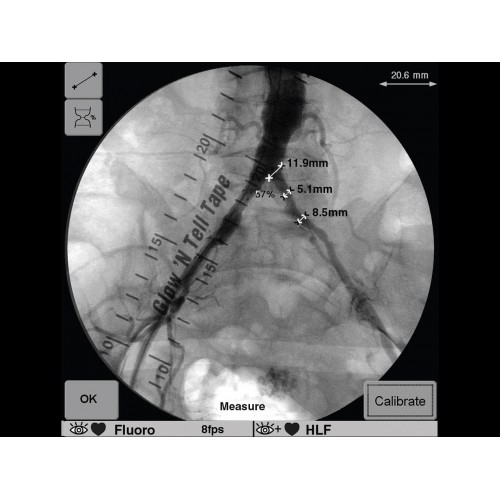

Инновационная мобильная С-дуговая система для интраоперационной визуализации с высоким разрешением. Обеспечивает хирургов качественным изображением в реальном времени при минимальной лучевой нагрузке. Усовершенствованная эргономика позволяет легко позиционировать аппарат в условиях операционной. Поддерживает интеграцию с современными хирургическими навигационными системами.

• Исключительное качество изображения для точного контроля операций

• Мощная система обработки изображений в реальном времени

GE OEC 9900 Elite оснащен революционной системой визуализации, обеспечивающей кристально четкое изображение анатомических структур. Интеллектуальная система автоматически адаптирует параметры исследования под конкретную хирургическую задачу, обеспечивая оптимальный баланс между качеством изображения и лучевой нагрузкой. Особое внимание уделено удобству работы операционной бригады.

В ведущих медицинских центрах GE OEC 9900 Elite успешно применяется для проведения сложных кардиологических, нейрохирургических и ортопедических вмешательств. Система доказала свою эффективность при выполнении стентирования коронарных артерий, эмболизации сосудов головного мозга и вертебропластики. Многие учреждения отмечают повышение качества операций после внедрения этого оборудования.